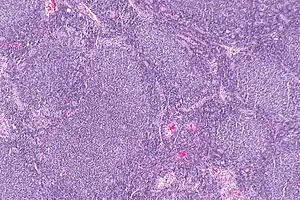

Follicular lymphoma (FL) is a cancer that involves certain types of white blood cells known as lymphocytes. The cancer originates from the uncontrolled division of specific types of B-cells known as centrocytes and centroblasts. These cells normally occupy the follicles (nodular swirls of various types of lymphocytes) in the germinal centers of lymphoid tissues such as lymph nodes. The cancerous cells in FL typically form follicular or follicle-like structures (see adjacent Figure) in the tissues they invade. These structures are usually the dominant histological feature of this cancer.[1]

| Micrograph of a follicular lymphoma, showing the characteristically abnormal lymphoid follicles that gave the condition its name. H&E stain. | |

The diagnosis of FL depends on examining involved tissues for histological, immunological, and chromosomal abnormalities that are indicative of the disease. FL usually involves enlarged lymph nodes populated by abnormal follicles (see adjacent picture) that when examined histologically contain a mixture of centrocytes or centroblast surrounded by non-malignant cells, mostly T-cells. The centrocytes, which typically outnumber centroblasts, are small to medium-sized B-cell lymphocytes that characteristically exhibit cleaved nuclei; the centropblasts are larger B-cell lymphocytes without cleaved nuclei.[11] Rare cases of FL may show lesions that contain tissue infiltrations dominated by B-cells with features of precursor (i.e. "blast") cells, monocytes, or malignant mantle cells such as those found in mantle cell lymphoma.[1] Immunochemical analyses reveal that the these cells generally express B-cell surface markers including the CD10 (60% of cases), CD20, CD19, CD22, and CD79 but not CD5, CD11c, or CD23 cell surface proteins;[4] genomic analyses reveal that these cells contain t(14:18)(q32:q21.3) translocation (85-90% of cases), 1p36 deletions (60-70% of cases), and with far less frequency the other genomic abnormalities listed in the above sections on Pathophysiology and Presentation and course. None of these protein markers or genomic abnormalities are diagnostic for FL, e.g. the t(14:18)(q32:q21.3) translocation is found in 30% of diffuse large B-cell lymphoma and in a small number of reactive benign lymph nodes. Rather, the diagnosis is made by a combination of histological, immunological, and genomic abnormalities.[4] According to World Health Organization (WHO) criteria, differences in the microscopically-determined morphology of these tissues can be used to diagnose and categorized FL into the following 3 Grades with grade 3 having A and B subtypes:[51]